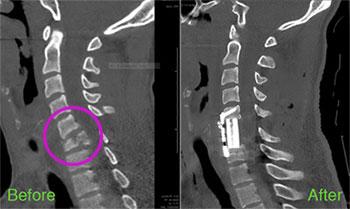

Nick was scheduled for surgery two days later. That's when he met Dr. Uzma Samadani, who sees a high volume of spinal fracture patients. "At HCMC, we deal with a lot of these types of injuries, unfortunately, with many patients traveling from great distances to see us. We have the expertise to manage these complex cases which are often referred by other neurosurgeons," said Dr. Samadani.

Dr. Samadani said that in the summer of 2016 when Nick had his accident, the emergency department had taken on an average of 2-3 spinal trauma cases per week. Most spinal fracture cases fall into three distinct categories: falls, motorcycle accidents, and diving accidents. Dr. Samadani sees each spinal fracture as a unique case. It's very important not to move the patient too much, which could cause paralysis. You have to be extremely careful.